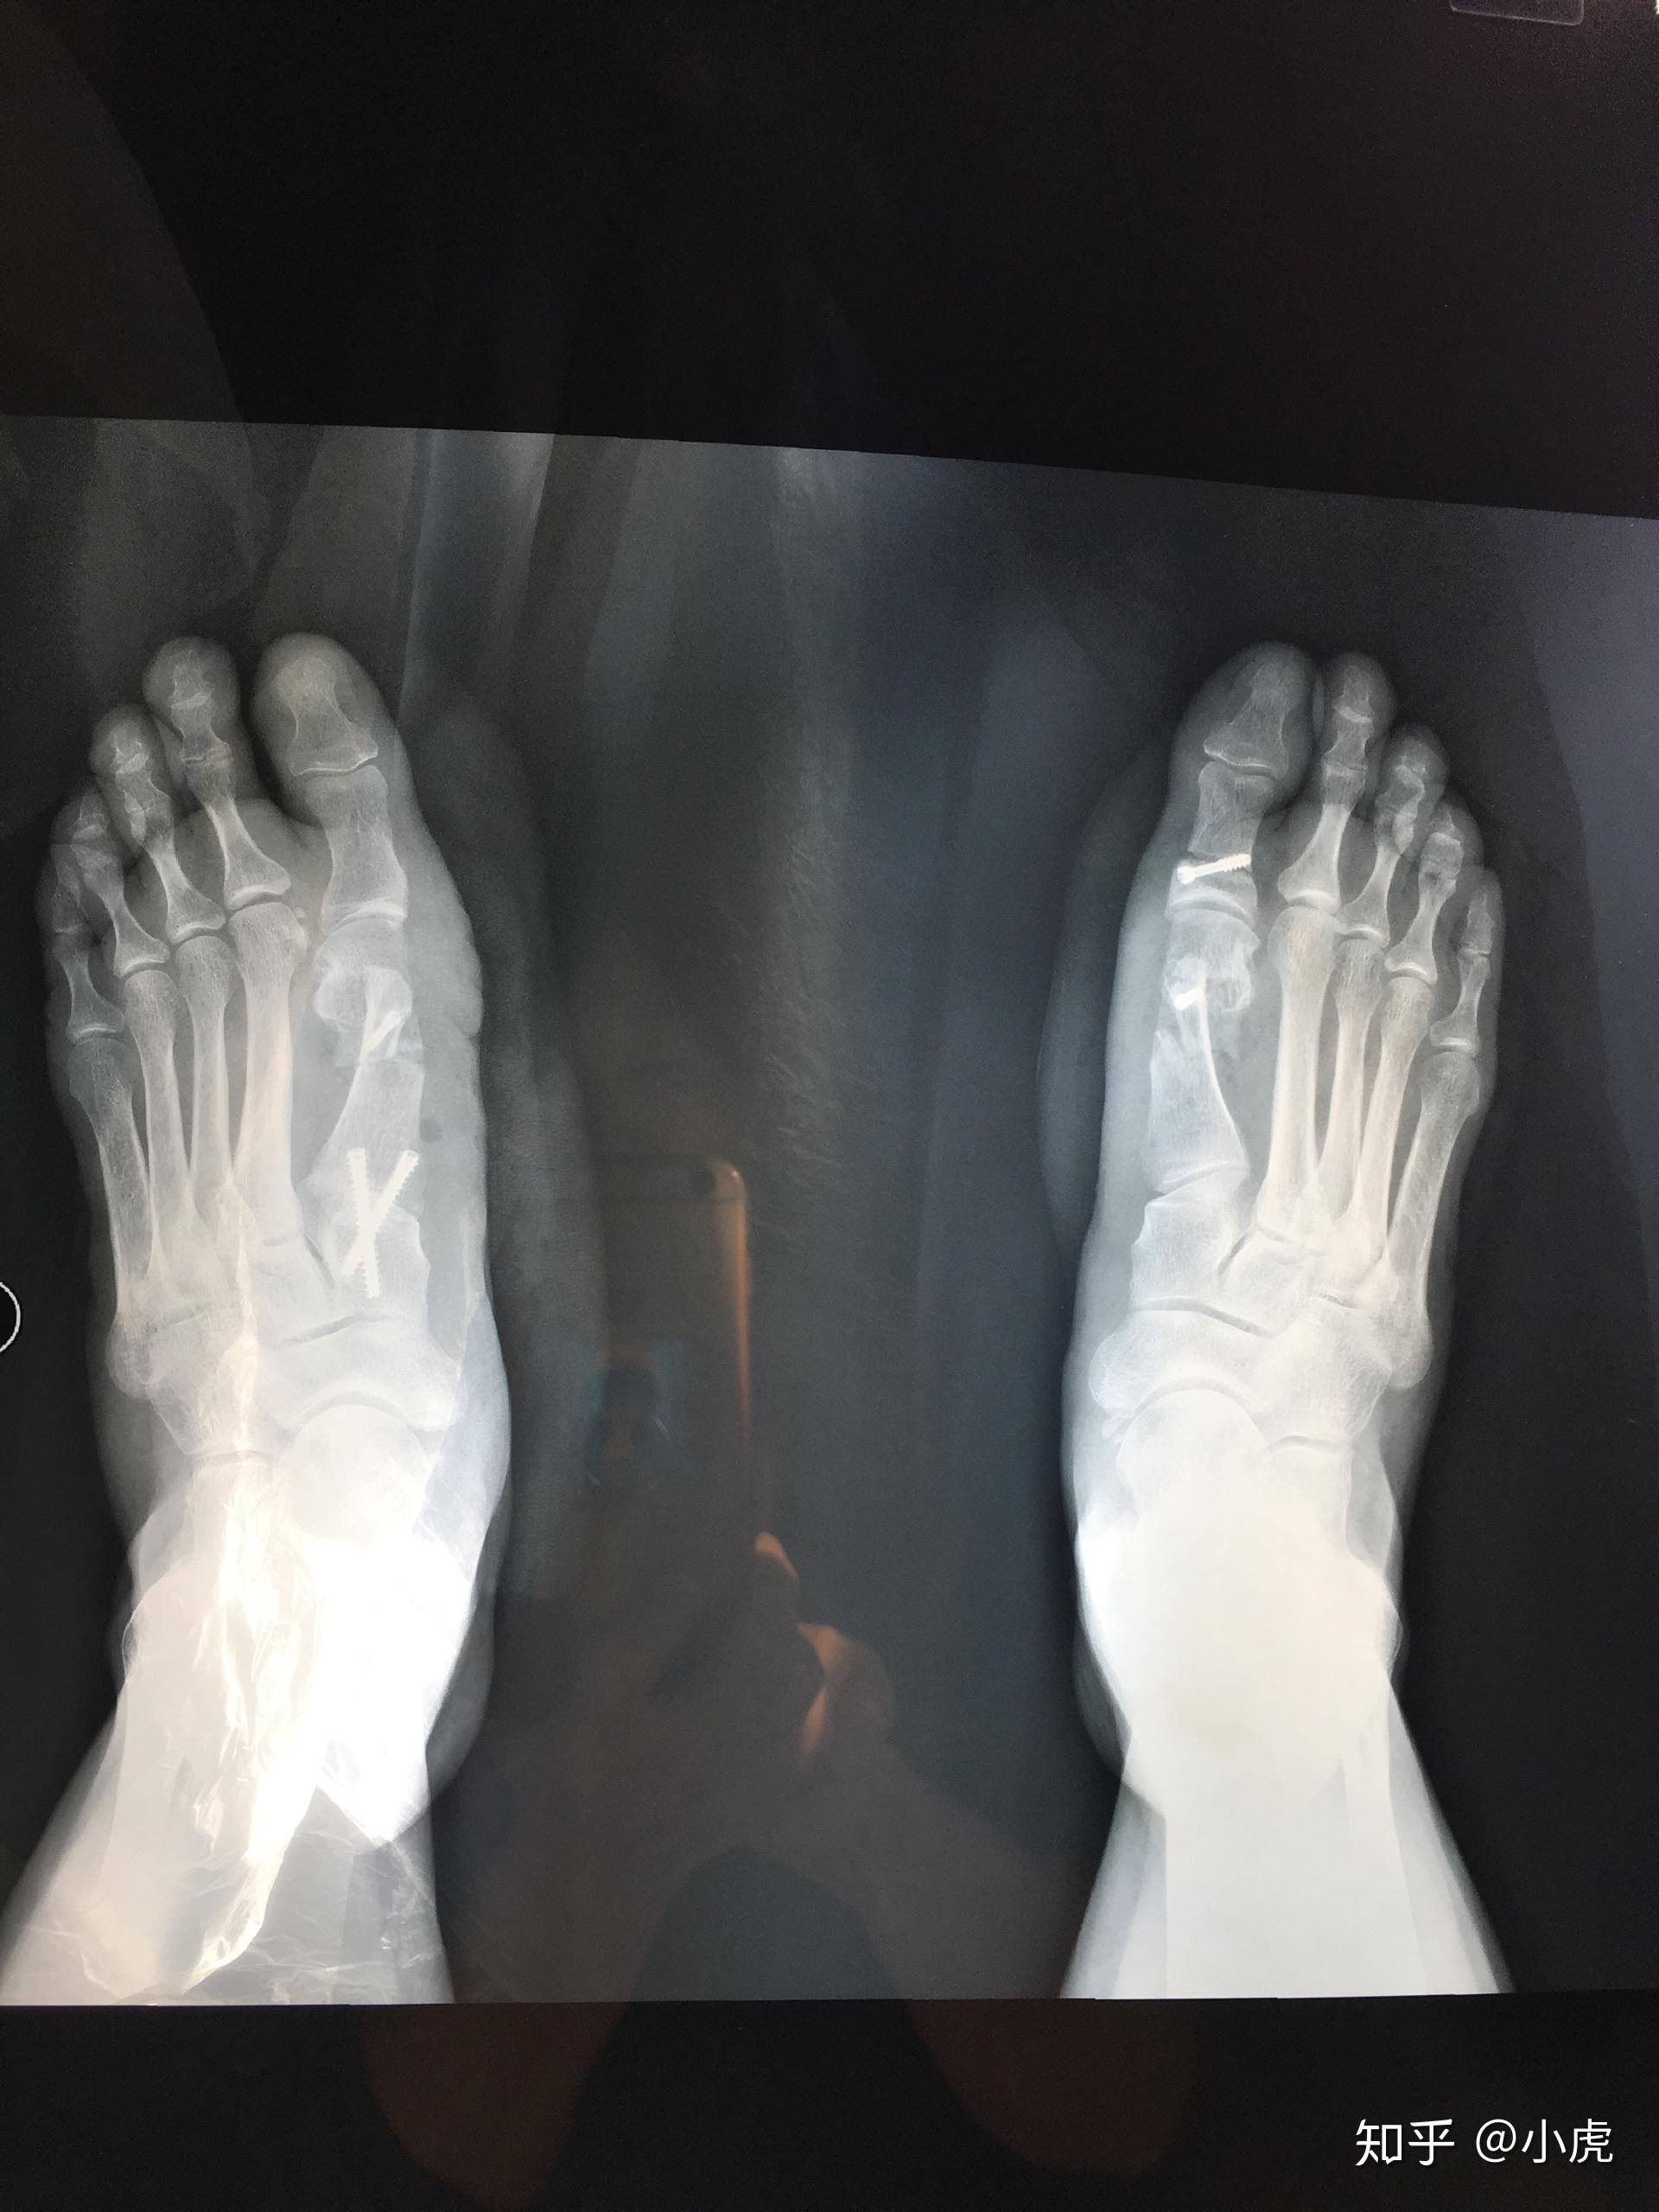

双足拇外翻的手术治疗

图片尺寸855x489